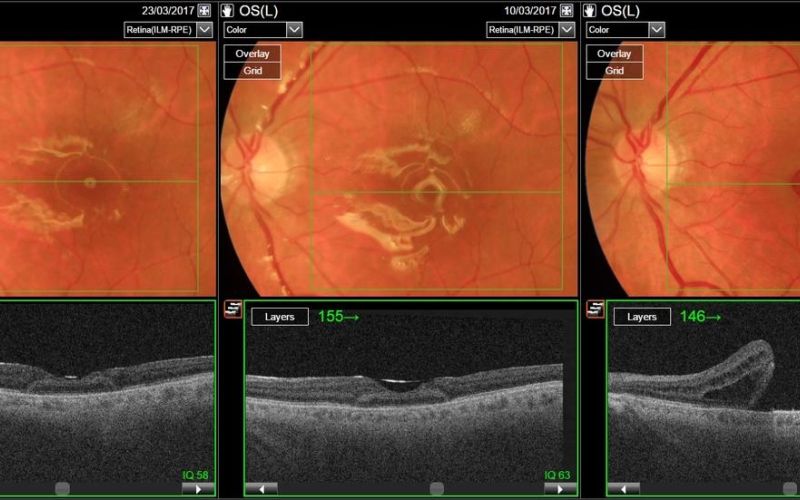

Z inovativnim posegom so pacientu rešili vid

Operacija avtologna presaditev mrežnice je edinstvena tudi v svetovnem merilu, saj je bilo takšnih posegov po nam dostopnih informacijah v svetu doslej opravljenih le približno 20.